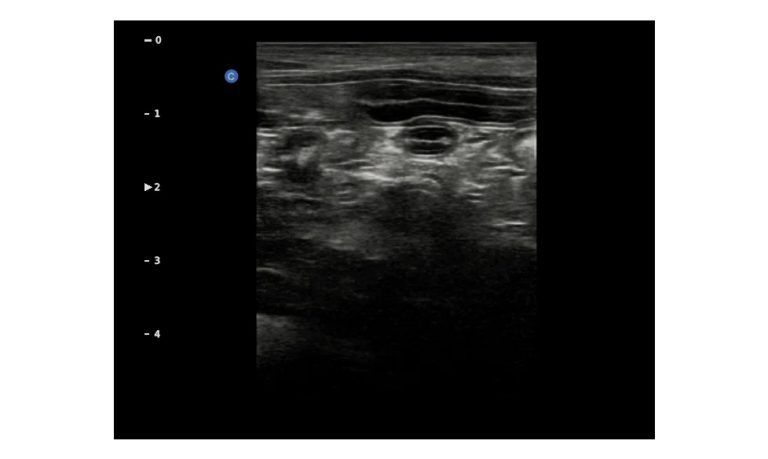

Esaote MyLab Sigma; So Fast, So Easy

Esaote’s new MyLab™SigmaVET is the smart, portable solution that allows use of an ultrasound whenever a quick and complete diagnosis is required.

- Dedicated VET software and probes

- Windows® 10

- Quick start-up

- Highly responsive capacitive touchscreen

- Pivoting 15.6” monitor2 probes connectors

- Easy to carry